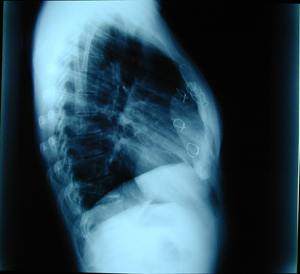

Περίπτωση Νο 2

Εικόνα 3

Η αξονική τομογραφία του θώρακος επιβεβαιώνει τα ευρήματα της απλής ακτινογραφίας του θώρακος και αναδεικνύει την ύπαρξη του όγκου του θωρακικού τοιχώματος προερχόμενο από την στερνοπλευρική γωνία στο ύψος της ξιφοειδούς απόφυσης. Ο όγκος έχει αποτιτανώσεις.